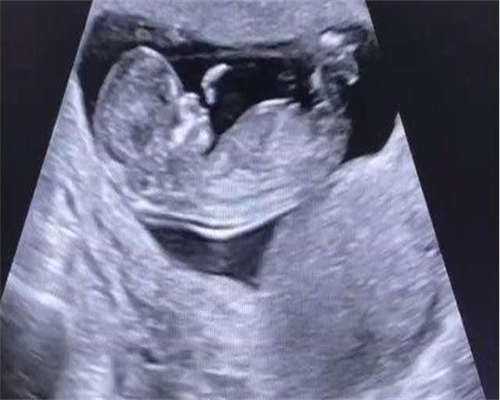

B超最早可在妊娠4-5周时看到孕囊,这时候就可以看到孕囊的具体位置。怀孕前三个月的时候,因为孕囊在宫腔中附着的并不是特别牢固,容易发生意外流产,所以在这个时候要注意不能过度活动,比如跑步,夫妻之间的性生活也是不可以的。

怀孕早期应该注意休息,尽量避免熬夜、劳累,记得补充叶酸,叶酸可以预防胚胎神经管发育畸形的,怀孕期间一定得定期做着围产保健检查,定期做彩超,看看胎儿发育的情况。